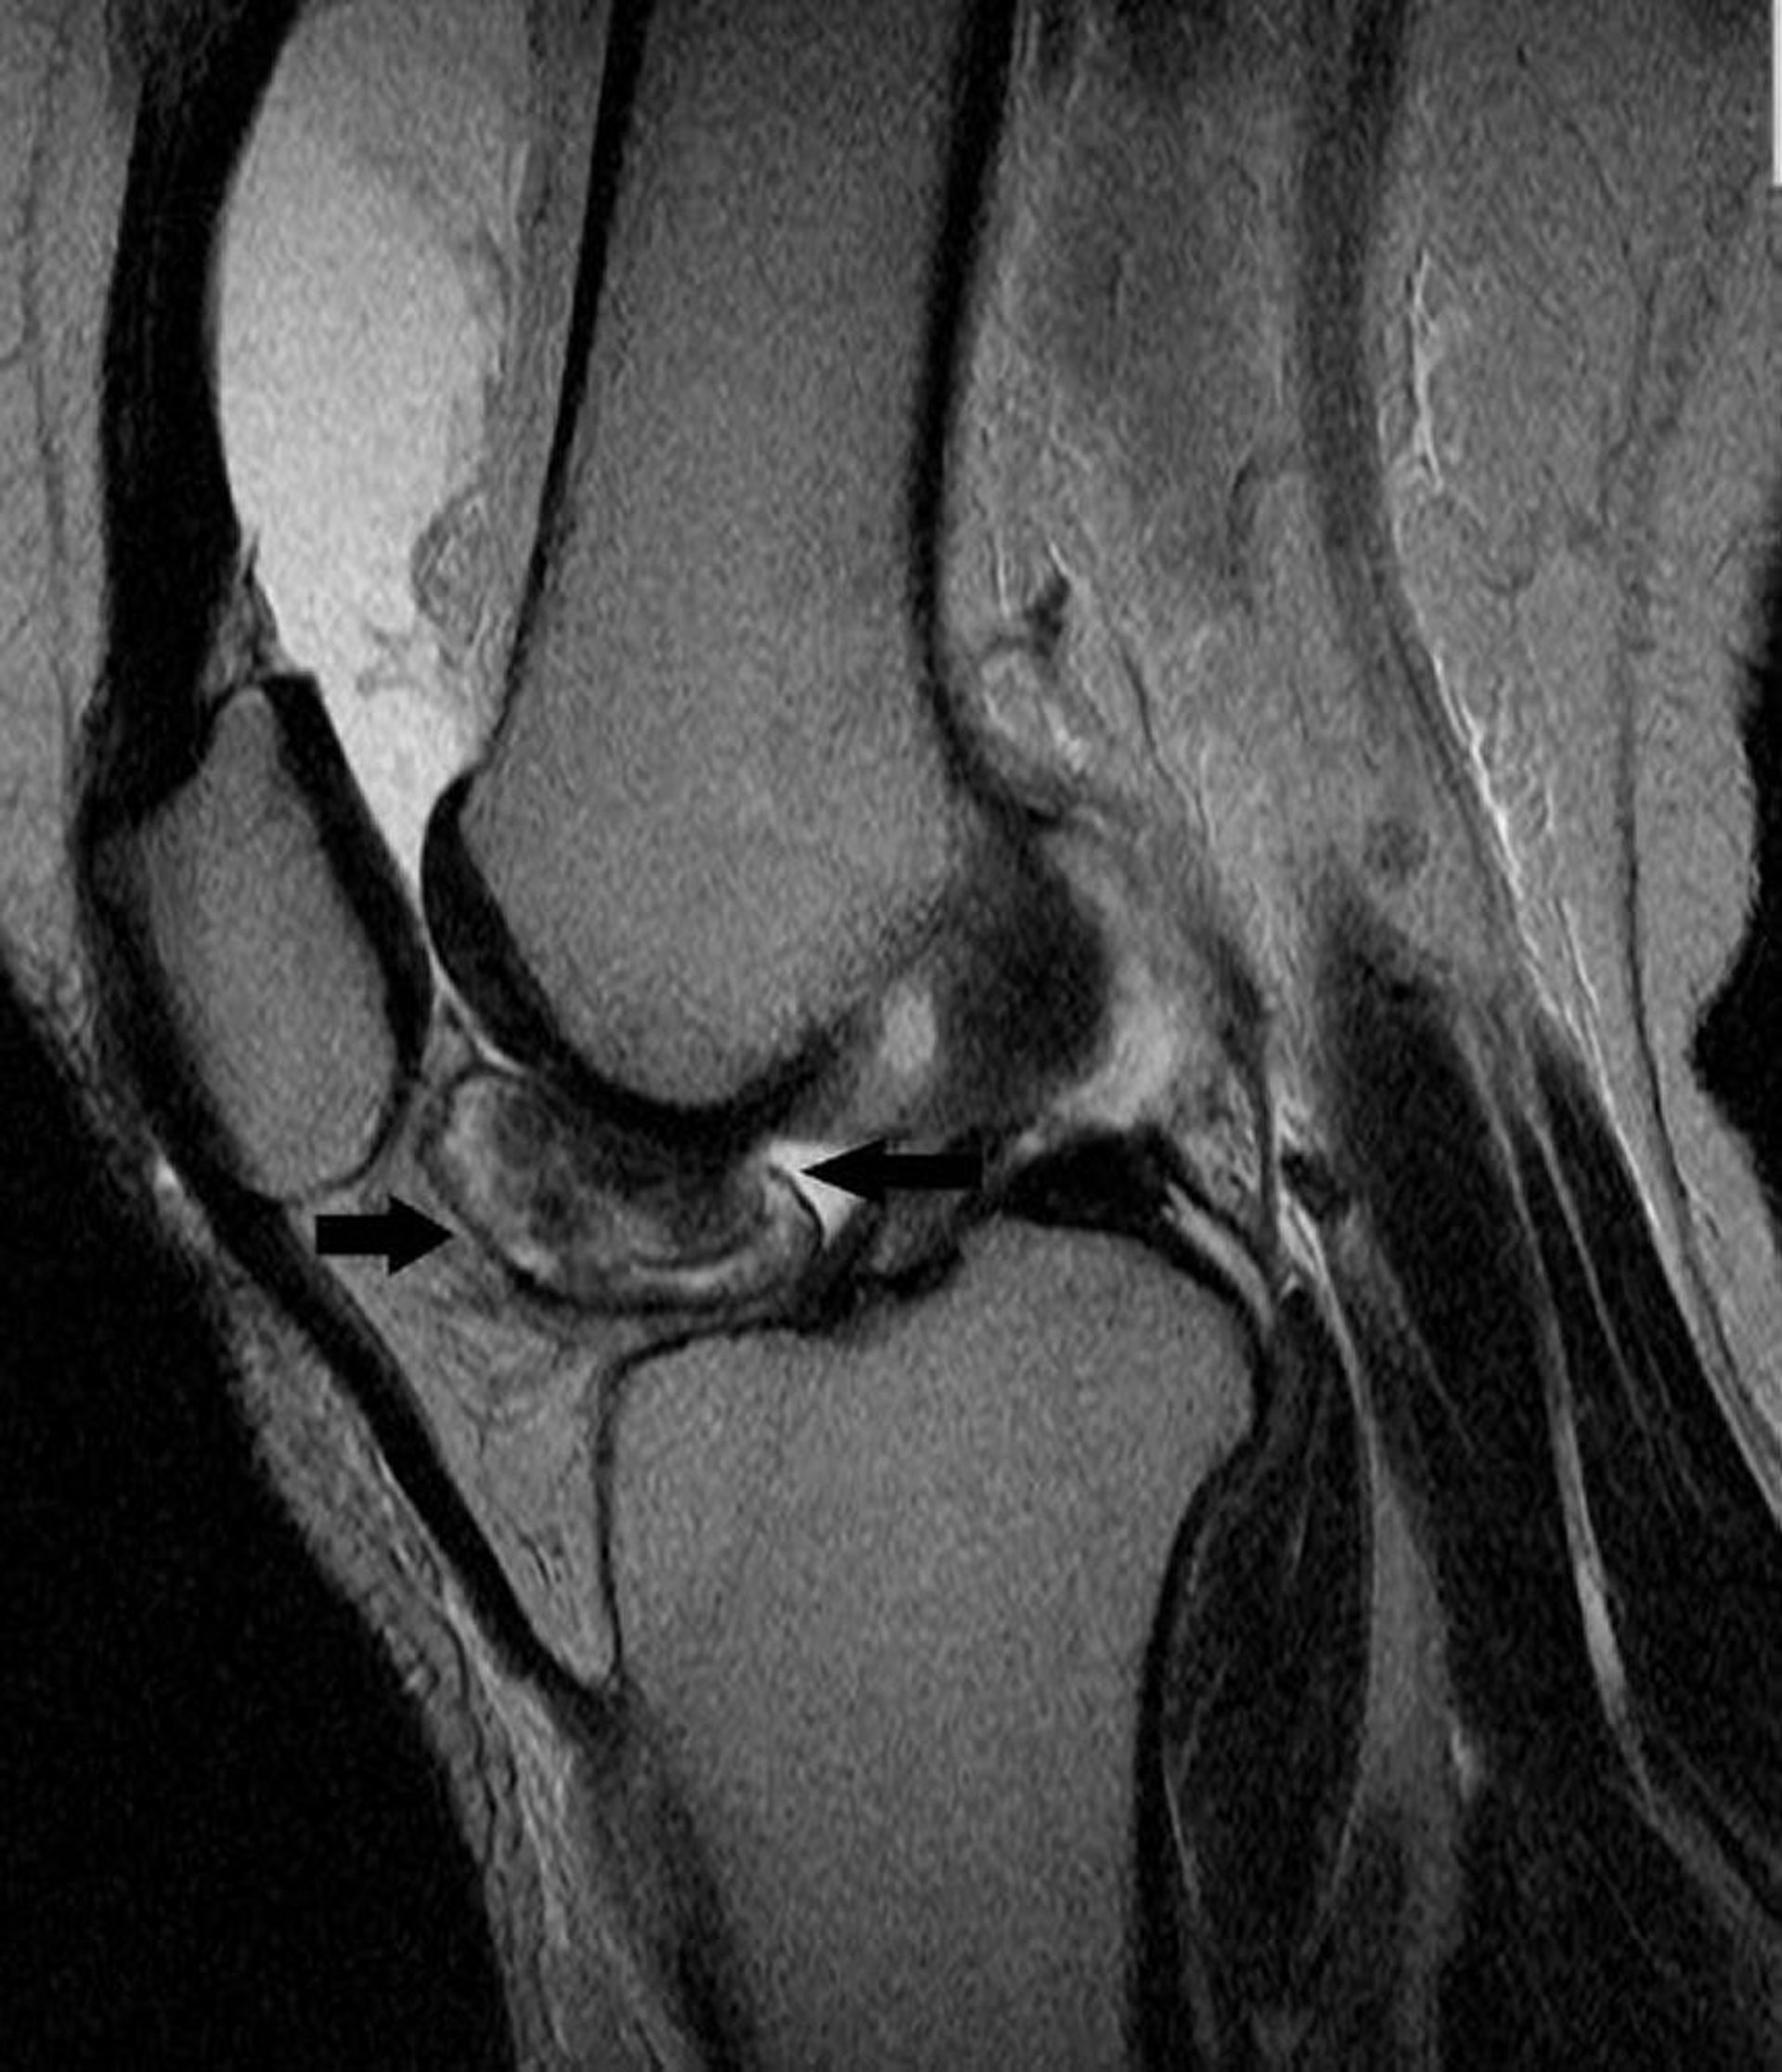

Hình ảnh MRI đầu gối này cho thấy khối u tế bào bao hoạt dịch khổng lồ hoạt dịch gân của khớp gối (mũi tên).

Hình ảnh do bác sĩ Michael J. Joyce, và bác sĩ Hakan Ilaslan cung cấp.